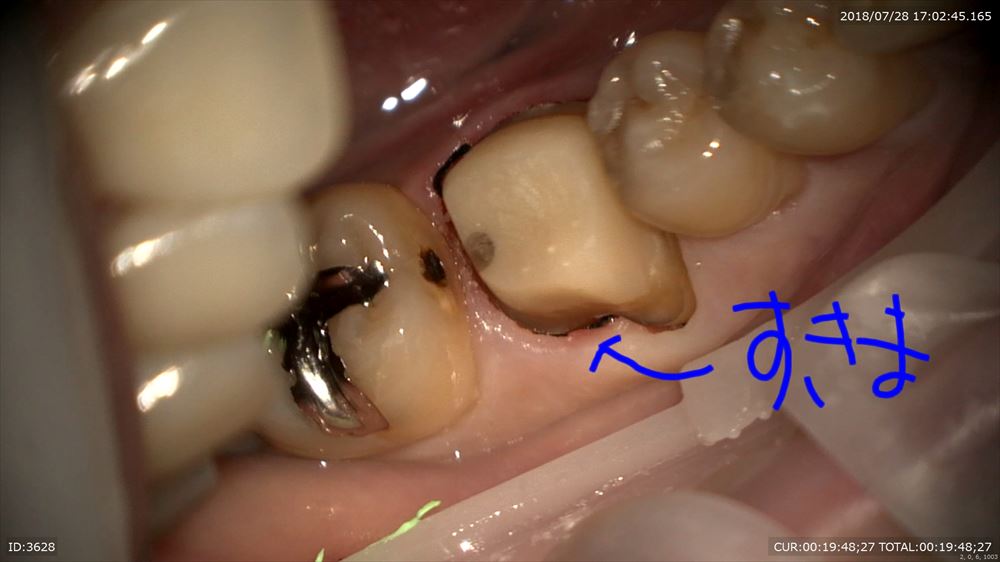

マイクロスコープを使用し準備

糸を入れるのは隙間を作るから。この緑を外すと

ここ。隙間ができここに型取りの材料を流します。

精密根管治療の予後は精密な型とりと精密な被せ物が重要だと報告があるようにこのステージが大切。